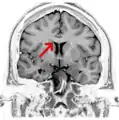

Coronal T2 (grey scale inverted) MRI of the brain at the level of the caudate nuclei emphasizing corpus callosum Coronal T2 (grey scale inverted) MRI of the brain at the level of the caudate nuclei emphasizing corpus callosum